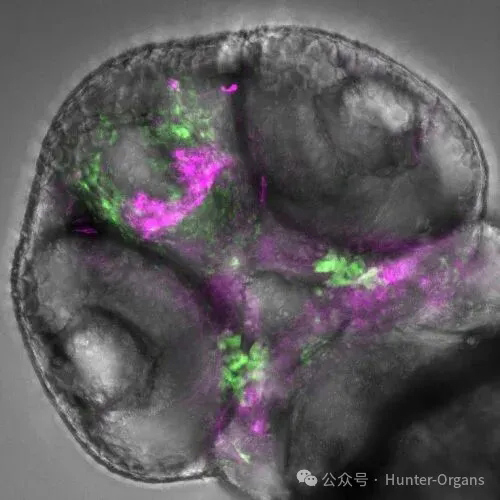

本研究利用斑马鱼,在肿瘤微环境中发现并命名了一种名为 “CRATER” (凹陷状生态位)的关键结构。该结构是肿瘤内部一个 “免疫友好型”的特殊区域,其中富含活跃增殖的CD8⁺ T细胞和特定的抗原呈递细胞,形成了一个促进免疫细胞识别和攻击癌细胞的局部环境。研究表明,CRATER结构的存在与患者对免疫检查点抑制剂治疗的积极反应和更长的生存期显著正相关。通过观察斑马鱼体内的黑色素瘤,发现CD8⁺ T细胞并非在肿瘤表明漫无目的地巡逻,而是在黑色素瘤边缘的凹陷区域聚集,与黑色素瘤细胞形成长时间的相互作用。通过斑马鱼进一步验证,揭示了调控CRATER形成的代谢机制,并提出靶向增强CRATER可作为改善癌症免疫治疗的新策略。